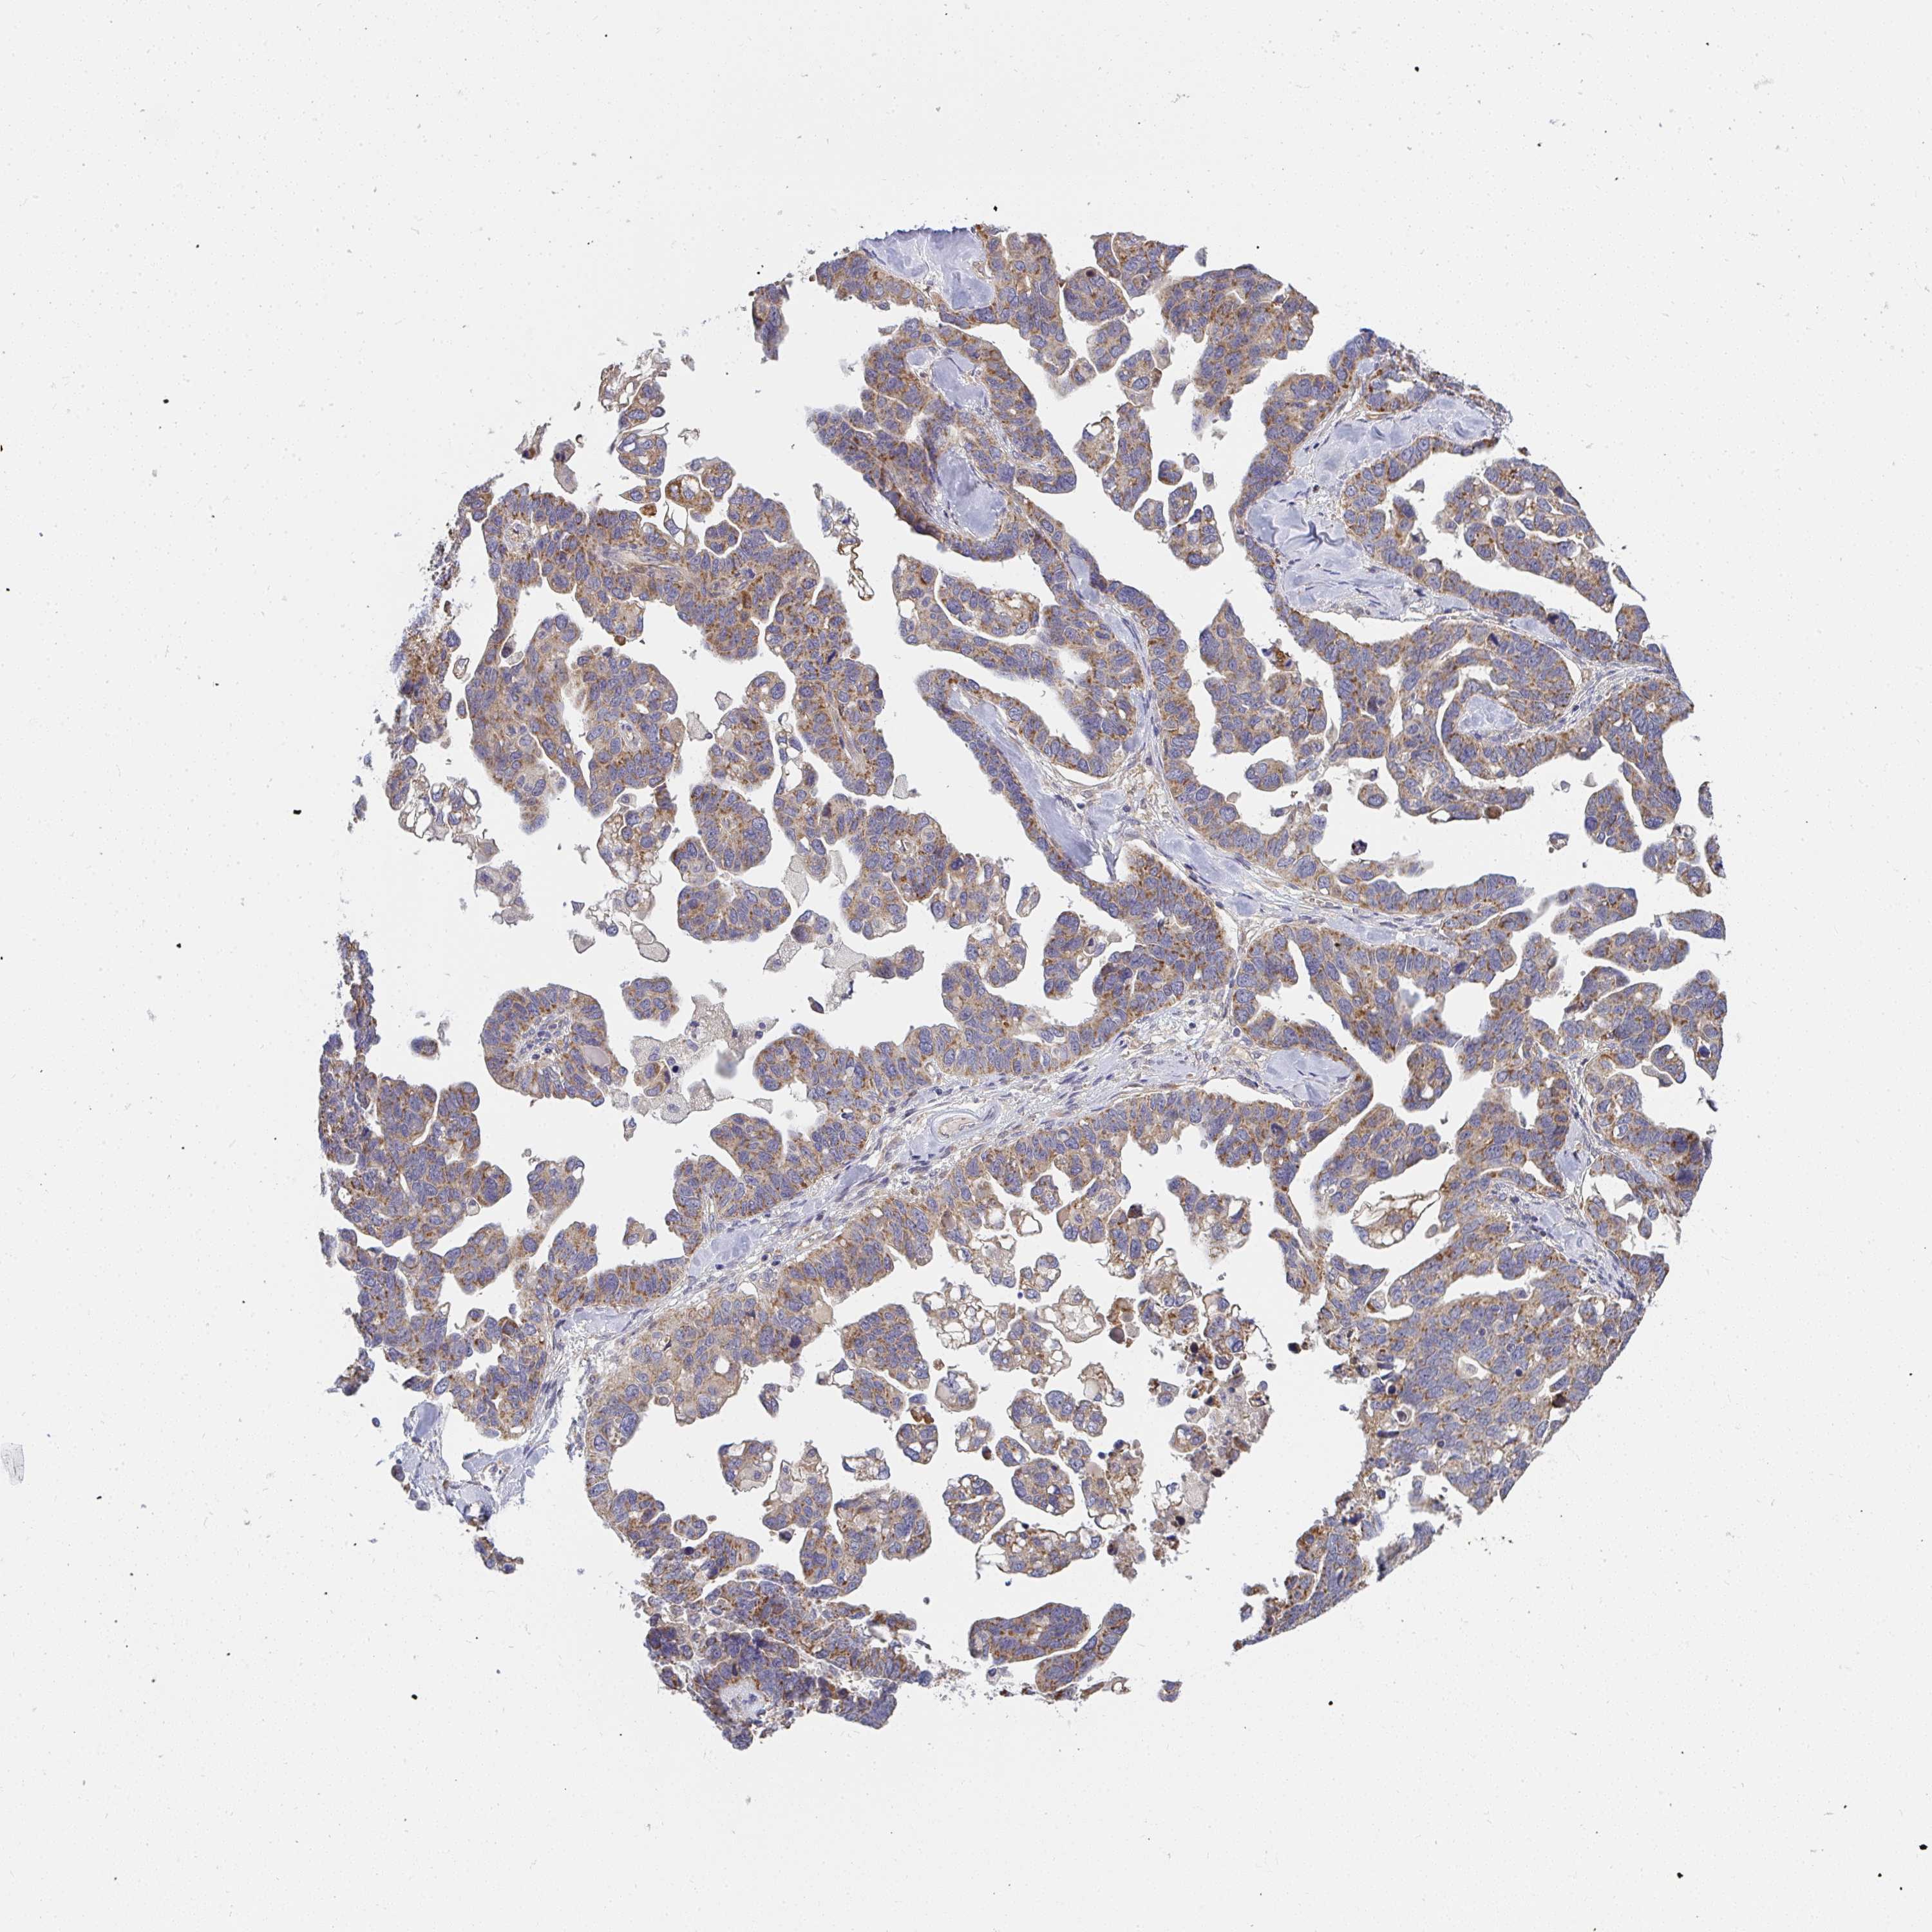

OVARIAN CANCER - Protein expressioni

A mouse-over function shows sample information and annotation data. Click on an image to view it in a full screen mode. Samples can be filtered based on level of antibody staining by selecting one or several of the following categories: high, medium, low and not detected. The assay and annotation is described here.

Note that samples used for immunohistochemistry by the Human Protein Atlas do not correspond to samples in the TCGA dataset.

Antibody stainingi

Antibody staining in the annotated cell types in the current human tissue is reported as not detected, low, medium, or high, based on conventional immunohistochemistry profiling in selected tissues. This score is based on the combination of the staining intensity and fraction of stained cells.

Each image is clickable and will lead to virtual microscopy that enables deeper exploration of all samples and also displays staining intensity scores, fraction scores and subcellular localization as well as patient and tissue information for each sample.

Antibody HPA058284

Antibody CAB020701

Cystadenocarcinoma, serous, NOS